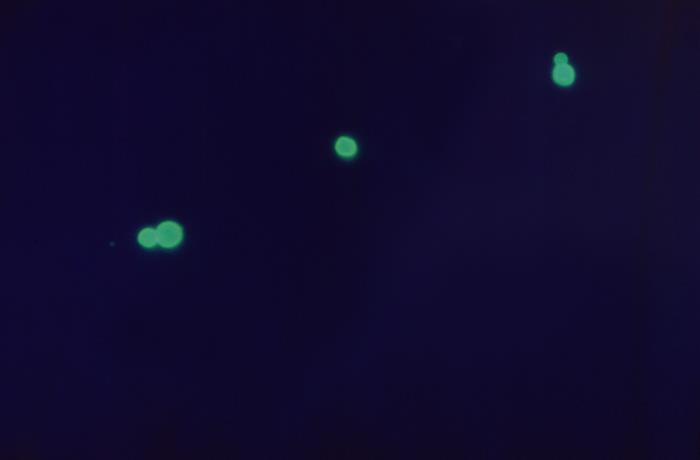

Under a magnification of 450X, and viewed using a fluorescent antibody (FA) staining technique, this photomicrograph revealed the presence of Cryptococcus neoformans, strain-B551 organisms, as evidenced by these glowing green fungal cells. This grouping was actually composed of two pairs of budding cells, and a single, C. neoformans cell.